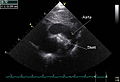

PDA is usually diagnosed using noninvasive techniques. Echocardiography (in which sound waves are used to capture the motion of the heart) and associated Doppler studies are the primary methods of detecting PDA. Electrocardiography (ECG), in which electrodes are used to record the electrical activity of the heart, is not particularly helpful as no specific rhythms or ECG patterns can be used to detect PDA.[3]

A chest X-ray may be taken, which reveals overall heart size (as a reflection of the combined mass of the cardiac chambers) and the appearance of blood flow to the lungs. A small PDA most often accompanies a normal-sized heart and normal blood flow to the lungs. A large PDA generally accompanies an enlarged cardiac silhouette and increased blood flow to the lungs.